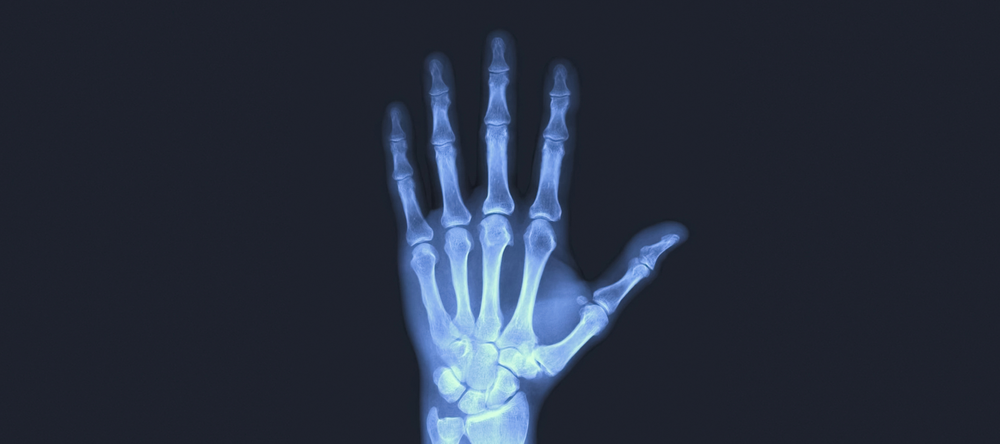

Celem projektu jest opracowanie nowych polimerowo-ceramicznych biomateriałów kompozytowych przeznaczonych do zastosowania w medycynie regeneracyjnej układu kostnego.

Kompozyty aktywne biologiczne to implanty, które mają zastąpić naturalną tkankę kostną, ale przede wszystkim przyspieszyć jej regenerację i sprawić by kość odbudowywała się prawidłowo, bez stanów zapalnych. Można więc powiedzieć, że wszczepiany implant „dekorujemy” substancjami, które wcześniej zostały przez nas przebadane i mamy pewność co do ich skuteczności.

Kompozyty mają kilka funkcji. Pierwsza z nich to stymulacja komórek kostnych do namnażania się i tworzenia tkanki kostnej (właściwości osteoindukcyjne). Druga, to działanie pro regeneracyjne, wspierające proces naprawczy komórek. Trzecia – przeciwdrobnoustrojowa (z użyciem antybiotyku). I kolejna, to działanie przeciwzapalne – czyli przeciwdziałanie reakcji zapalnej, która działałaby na niekorzyść procesu gojenia.

Kolejną ważną funkcją implantu jest biozgodność. Implant nie może być toksyczny ani powodować alergii i drażnić komórek.